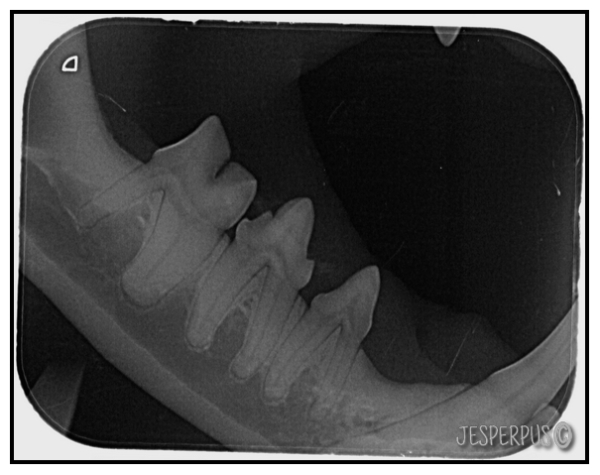

Etter plakkfjerning ble tigertennene slik:

Litt rødt tannkjøtt, men det blir borte etter noen dager.

Helt rene, fine og hele tenner og ingen tannsykdommer å se